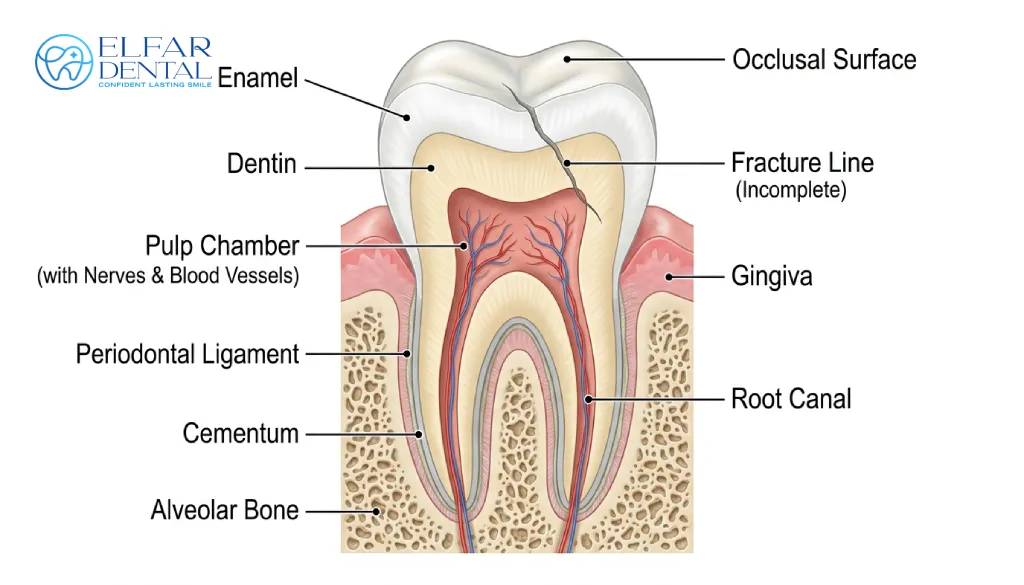

Cracked Tooth Syndrome: Causes, Symptoms & Treatment – Elfar Dental

Mysterious tooth pain when chewing? It could be cracked tooth syndrome. Learn the signs, diagnosis, and